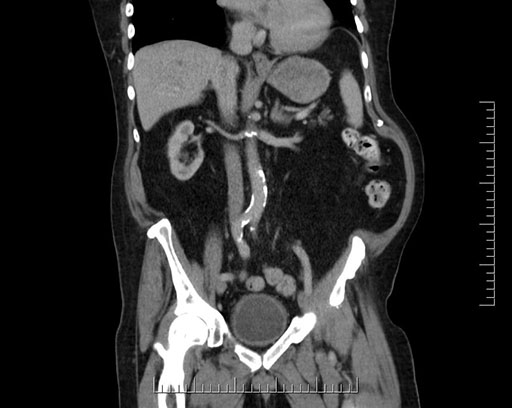

Coronal - stented